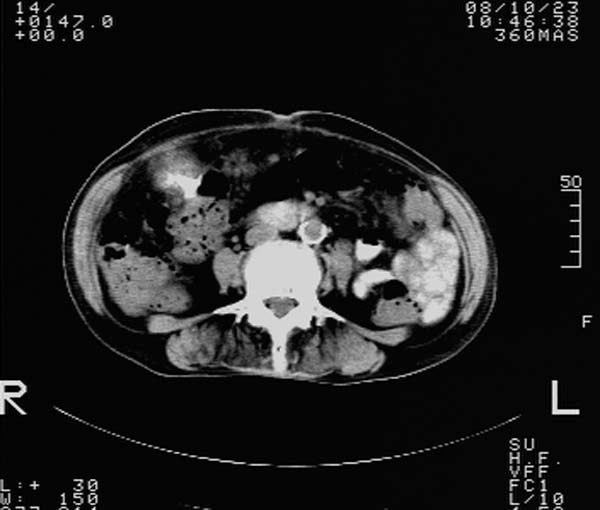

f,67y。反复右上腹痛。余无异常。

前五幅未服造影剂。后面图像有上传重复的。请战友们发表意见。

胆囊结石、胆囊癌伴邻近脏器受侵,不除外黄色肉芽肿性胆囊炎,建议增强扫描。肝多发囊性占位性病变,囊肿或囊性转移。

胆囊内结石,胆囊壁不规则增厚,胆囊胃窦区解剖结构欠清晰,楼主提示为少见病,考虑bouveret综合征?黄色肉芽肿性胆囊炎?肝内多发低密度占位,建议增强或b超